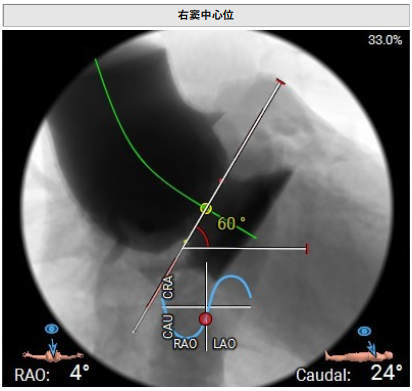

术前影像评估提示,患者主动脉瓣为三叶瓣,分布较均匀,无明显钙化。主动脉瓣环直径约25.5mm,左室流出道直径27.7mm,STJ直径49.9mm,升主动脉直径45.4 mm,冠脉开口高度充足(左冠12.4mm,右冠11.6mm),梗阻风险低。入路角度方面,左室-主动脉夹角为150°,心脏角度60°。

术中回顾及效果

手术过程顺利。术中通过右窦居中造影、定位件入窦造影及释放后功能确认等关键步骤,确保瓣膜锚定准确。器械用时仅10分钟。术后患者主动脉瓣重度反流纠正,无反流、无瓣周漏。心脏彩超显示人工生物瓣启闭良好,平均跨瓣压差4mmHg,流速正常。患者恢复情况良好,心脏功能得到显著改善。